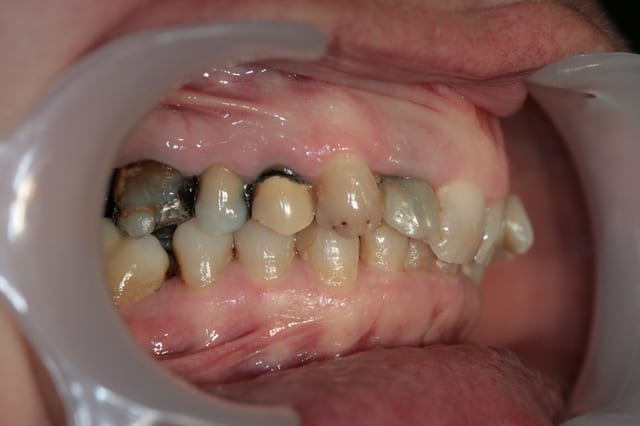

Tous est à refaire dans cette bouche, amalgames horibles, couronne brisée, etc

Donc la suite, évidement ortho: ingression du bloc incisivo canin sup avec ré alignement des arcades, extraction de la 14 nécessaire et ré alignement des milieux interincisif.

Pendant la finalisation du haut (axe mésio-disto incisif, à corriger à la fin pour faciliter gingivoplastie incisif sup). Il y a eu composite vestibulaire pelliculaire sous digue de 33 à 43, reprise soins et ancrage + provisoires 34,35, 36, 46; et composite sous digue 37 et 47.

Si bien sûr, sur les photos le bas venait juste d'être déposé, pour le montage composite, la patiente retournait le lendemain chez l'ortho pour placer une contention (celles que je fais avec l'Everstik me semble moins costaud que les siennes avec un fil titane), on devine un peu les faces vestibulaires des inf sur les photos pstés précédement, elles ont un sorte de crevace les striant de mesial à distal à mi hauteur, avec des petits trous colorés brun , mais pas de lésion carieuse ni de restauration ancienne. Le haut devait être déposé dans la foulé mais l'axe mésio-distal des 11 et 21 était trop couché et c'est moche (effet d'essuie glace) donc le multibague haut est resté quelques semaines de plus, d'où les photos mixte soins bas ortho haut.